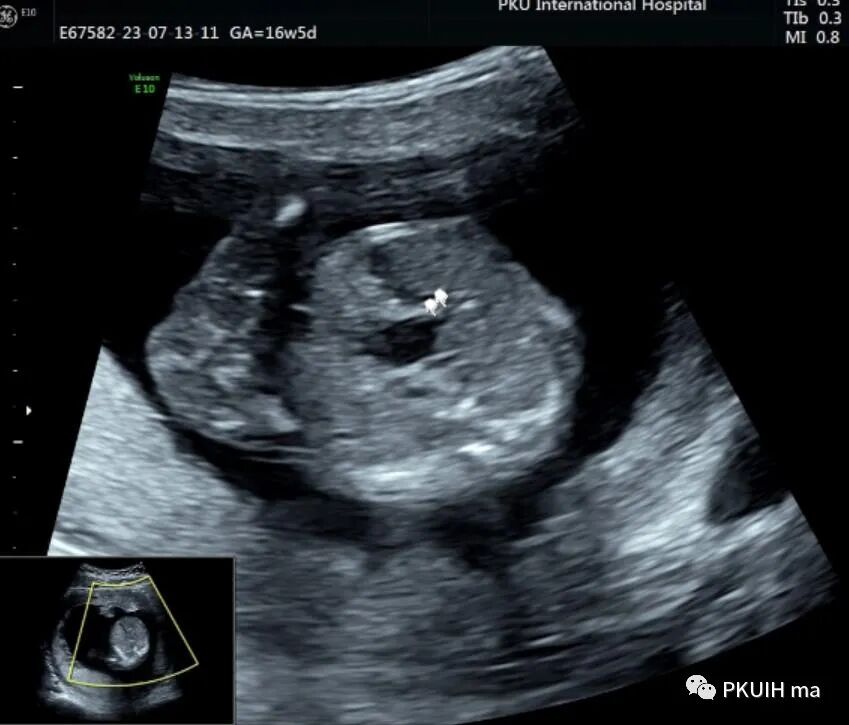

孕妇16周+5天常规超声检查发现腹部一囊性包块,如下图

胎儿中腹部见一囊性包块,大小约1.2x1.0x0.8cm,边界清,形态规则,内透声好。囊肿位于脊柱前方、胆囊后方、门静脉窦旁,与后肾接近

观察囊肿与肾、胃泡、膀胱均无相关。

仔细观察囊肿壁好像不完整,周边见微小管道回声与囊肿相通

CDFI:囊肿内未见明显血流信号。

由于囊肿位于胆囊后方、肝下方、门静脉窦旁,随考虑为胆总管囊肿